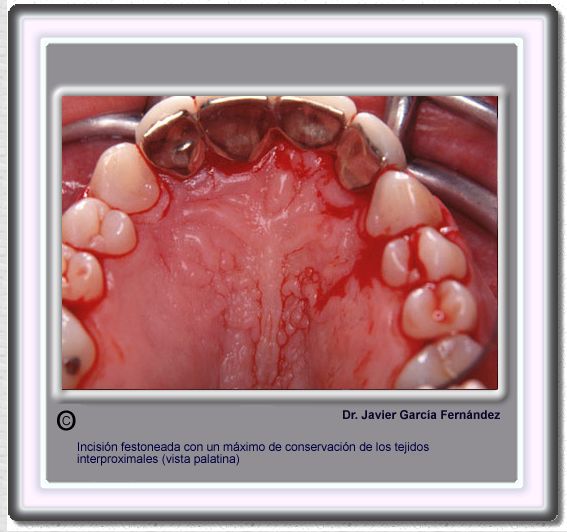

image 186